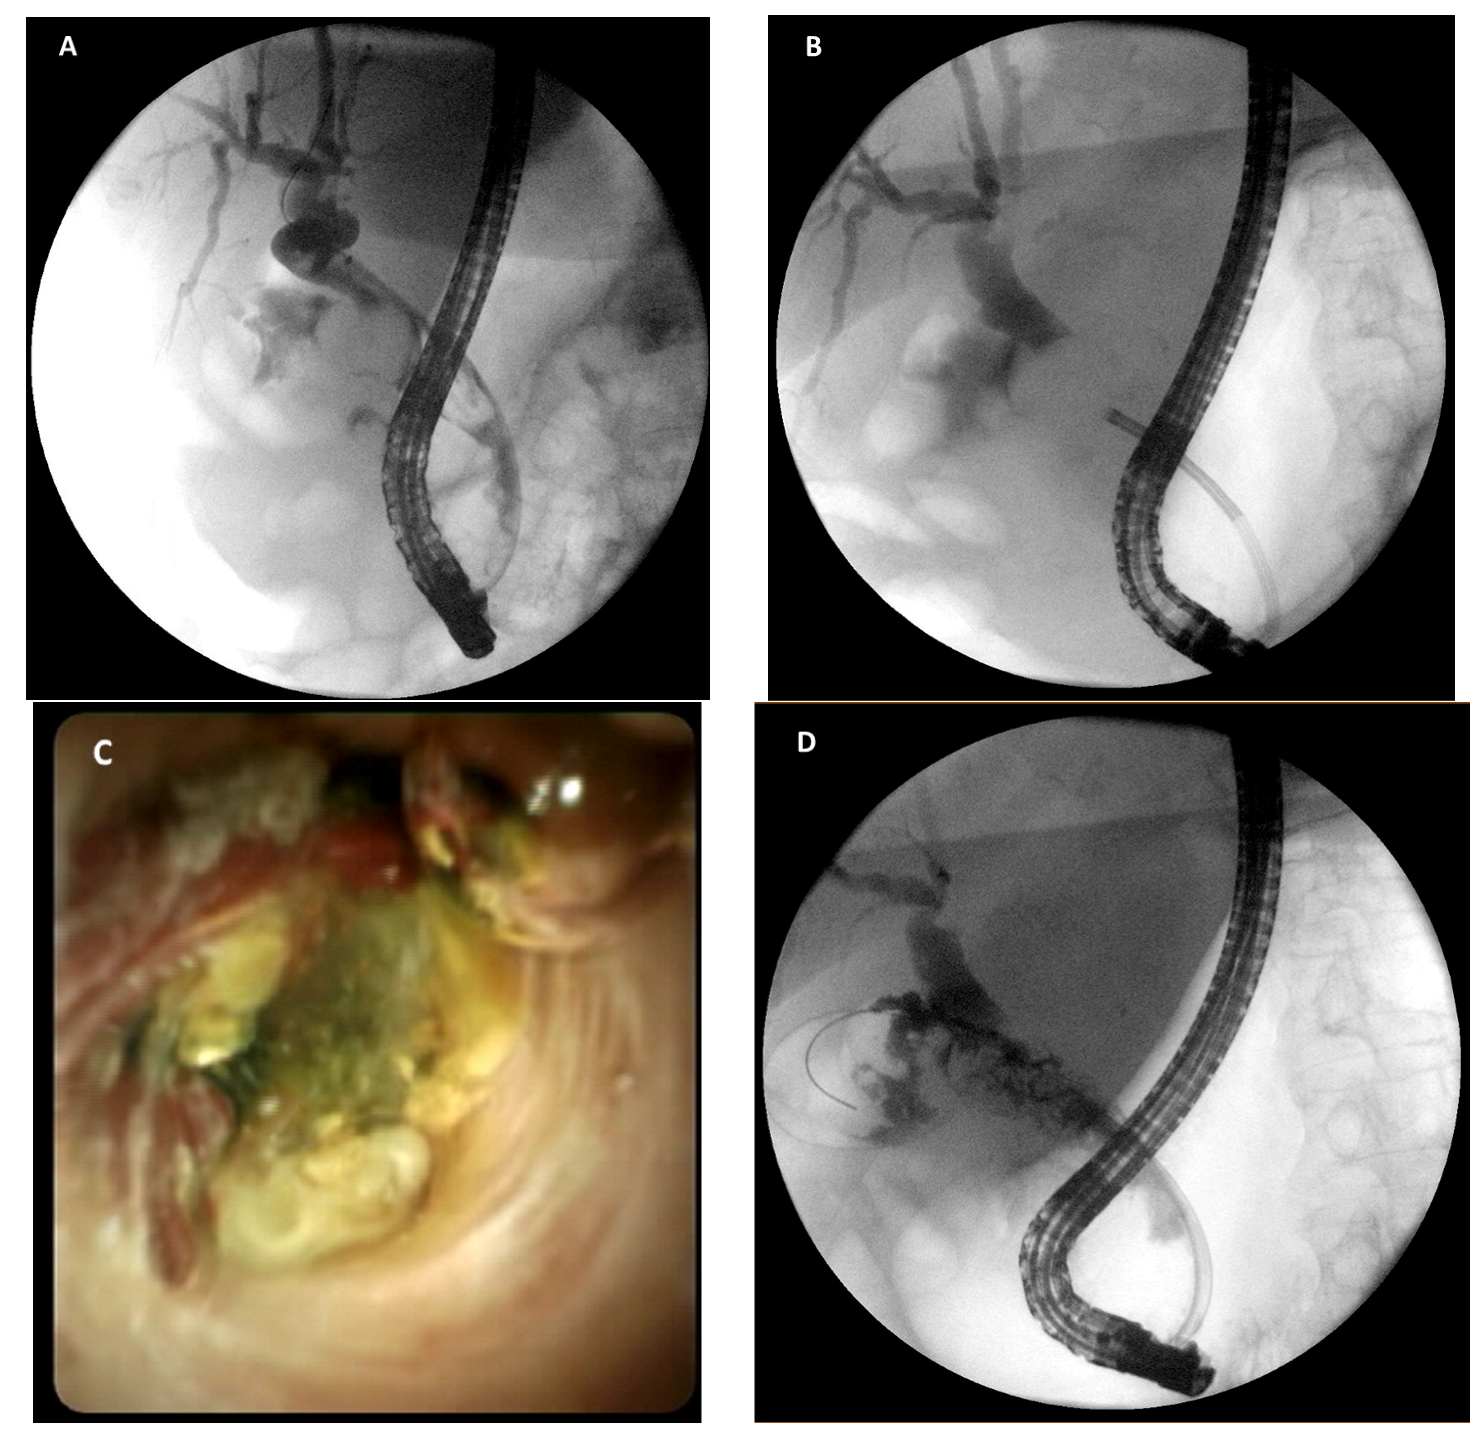

- Bhandari, S.; Bathini, R.; Sharma, A.; Maydeo, A. Usefulness of single-operator cholangioscopy-guided laser lithotripsy in patients with Mirizzi syndrome and cystic duct stones: Experience at a tertiary care center. Gastrointest. Endosc. 2016, 84, 56–61. [Google Scholar] [CrossRef] [PubMed]

- Chon, H.K.; Park, C.; Kim, T.H. Minimally Invasive Approach Using Digital Single-Operator Peroral Cholangioscopy-Guided Electrohydraulic Lithotripsy and Endoscopic Nasogallbladder Drainage for the Management of HighGrade Mirizzi Syndrome. Clin. Endosc. 2021, 54, 930–934. [Google Scholar] [CrossRef]

- Binmoeller, K.F.; Thonke, F.; Soehendra, N. Endoscopic treatment of Mirizzi’s syndrome. Gastrointest. Endosc. 1993, 39, 532–536. [Google Scholar] [CrossRef]